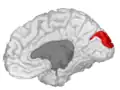

Cuneus

Medial surface of left cerebral hemisphere. (Cuneus visible at left in red.)